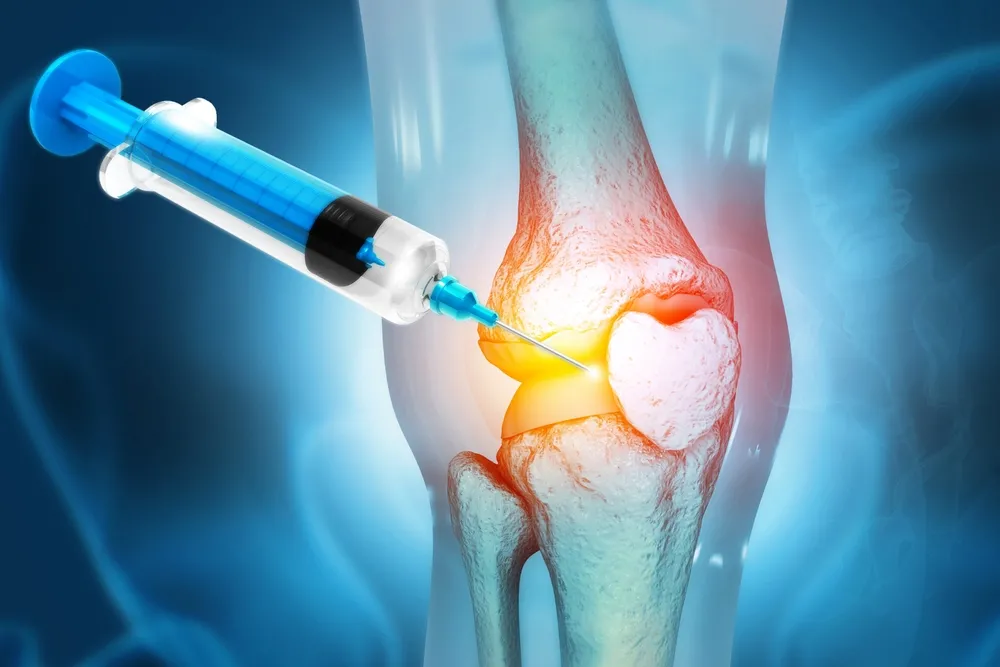

Utilizamos técnicas mínimamente invasivas para una recuperación eficiente y cómoda

Utilizamos tecnología de vanguardia y técnicas quirúrgicas innovadoras para garantizar los mejores resultados posibles para sus pacientes.

Egresado de la Universidad San Luis Gonzaga de Ica, con estudios de posgrado en la Universidad Federico Villarreal. Con más de 15 años de experiencia, el Dr. Vladimir Inca se ha especializado en el tratamiento de fracturas, lesiones articulares y cirugías de prótesis. Su enfoque se basa en brindar atención personalizada y soluciones efectivas para mejorar tu calidad de vida y recuperar tu movilidad.